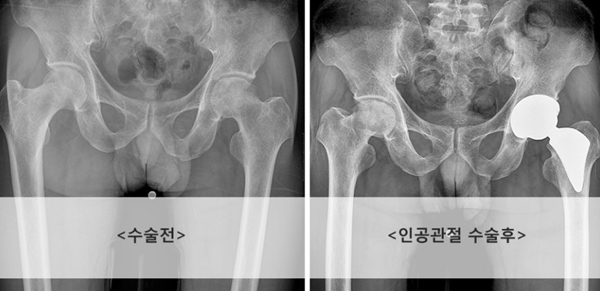

| [건강설계]고관절 연골 손상, 신체 균형까지 틀어져 | |||||

[건강설계]고관절 연골 손상, 신체 균형까지 틀어져 |